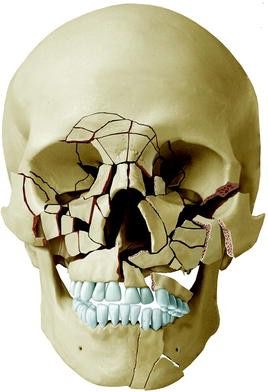

Emergency treatment for injuries affecting the face, mouth, and jaws. This includes repairing broken or dislodged teeth, treating fractured jawbones (mandible/maxilla), repairing cuts to the gums and lips, and managing facial wounds.

Immediate treatment is crucial to restore full function, minimize scarring, and prevent severe long-term complications. Prompt care ensures fractures heal correctly and saves as many natural teeth as possible.

This depends entirely on the nature of the injury. If you have any jaw fractures or significant soft tissue repair, you will likely be on a liquid or extremely soft diet for several weeks. Follow your surgeon's specific instructions meticulously.